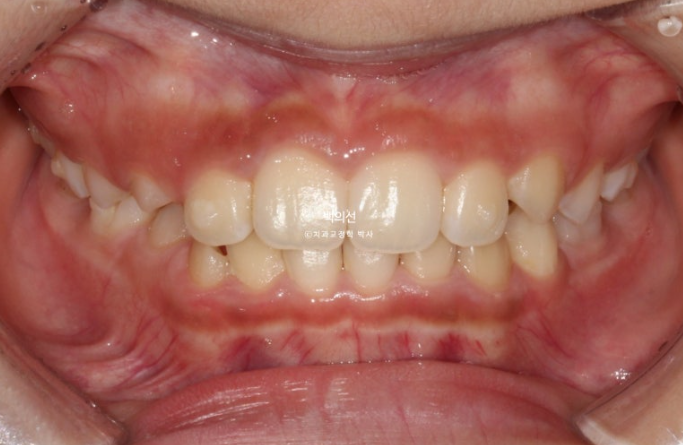

과개교합은 개선이 되어 아래앞니가 보이고 중심선은 잘 맞습니다.

앞니 뻗침과 돌출은 해결이 되었고 그 사이 남아있던 유치가 여러개 빠졌습니다.

좁았던 악궁이 넓어지면서 모양이 잡혔고

24.02

삐뚤했던 아래 앞니는 가지런해졌고 송곳니는 악궁확장을 통해 공간이 생기면서 제자리로 잘 올라오게 되었습니다.